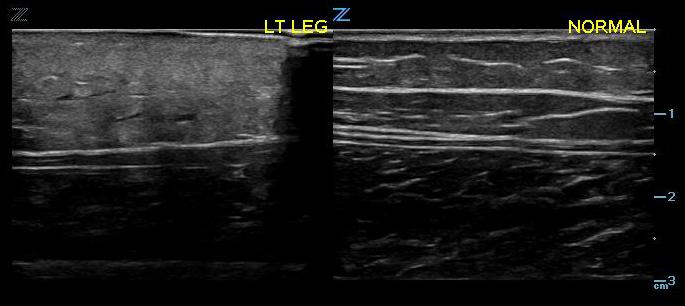

- Figure 3. Early cellulitis (left) compared with normal (right)

- The initial appearance may be generalized swelling and increased echogenicity of the skin and subcutaneous tissues (Fig. 5).9,10